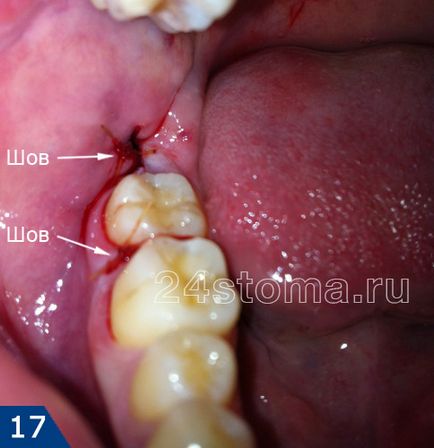

Накладення швів (рис.3). Зашивання рани шовним матеріалом необхідно для того, щоб зблизити краї рани. По-перше - ясна після відшарування гладилкою трохи бовтається, тому кров'яний згусток може випасти з лунки. Накладення швів дозволить попередити випадання згустку і до того ж дозволить рані швидше зажіть.Во-друге, коли розмір рани зменшується завдяки швах - це різко знижує сам ризик розвитку запалення лунки зуба, тому що зменшується розмір вхідних воріт для інфекції, якою досить в порожнині рота.

По-третє - шви накладаються в разі, коли потрібно зупинити кровотечу. Але вони також допомагають попередити кровотечу, яке іноді виникає у пацієнтів вже через кілька годин після видалення. Знімаються шви приблизно на 5-10 день. У разі якщо використовується кетгут, то шви не знімаються, тому що кетгут розсмоктується сам.